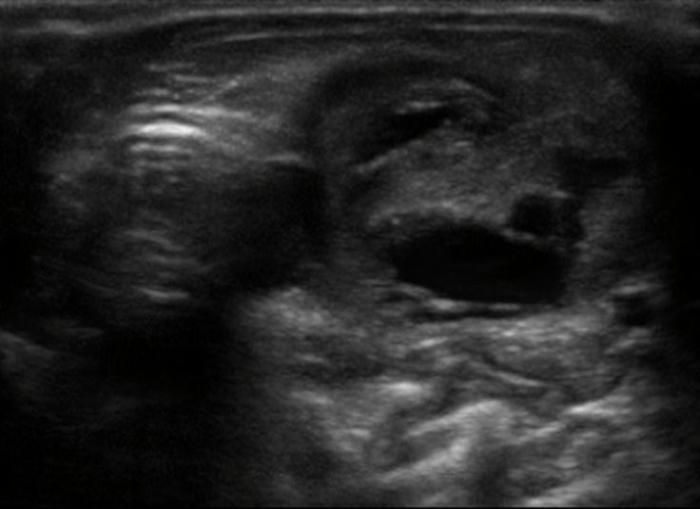

El hipertiroidismo felino, endocrinopatía común en gatos geriátricos, se caracteriza por una hipertrofia glandular funcional, frecuentemente bilateral, aunque puede presentarse en forma asimétrica o unilobular17. Los hallazgos ecográficos incluyen aumento del tamaño tiroideo, contornos irregulares, parénquima hipo o mixto-ecogénico, y pérdida de la arquitectura homogénea (Figura 12A-B), con lesiones cavitarias internas (Fgura 13A-D). Es común observar nódulos de pequeño tamaño (<10 mm), bien delimitados y con vascularización periférica o central aumentada al Doppler color9.

Los estudios de seguimiento postratamiento han evidenciado una reducción significativa del volumen glandular tras terapias con metimazol o radioyodo, observándose una reaparición progresiva de la homogeneidad parenquimatosa en algunos casos10. Sin embargo, en gatos con recaídas clínicas o mala respuesta, la glándula puede mantener un patrón nodular persistente o desarrollar mineralización distrófica19.

Las neoplasias tiroideas son menos frecuentes en gatos que en perros y, cuando ocurren, suelen corresponder a adenomas funcionales. No obstante, se han documentado casos de carcinomas, los cuales pueden imitar ecográficamente al patrón nodular benigno, aunque con mayor tendencia a la invasión local, pérdida de la cápsula y vascularización desorganizada13 (Figura 14). Por ello, la ecografía debe ser interpretada junto con los hallazgos clínicos, bioquímicos y eventualmente citológicos.